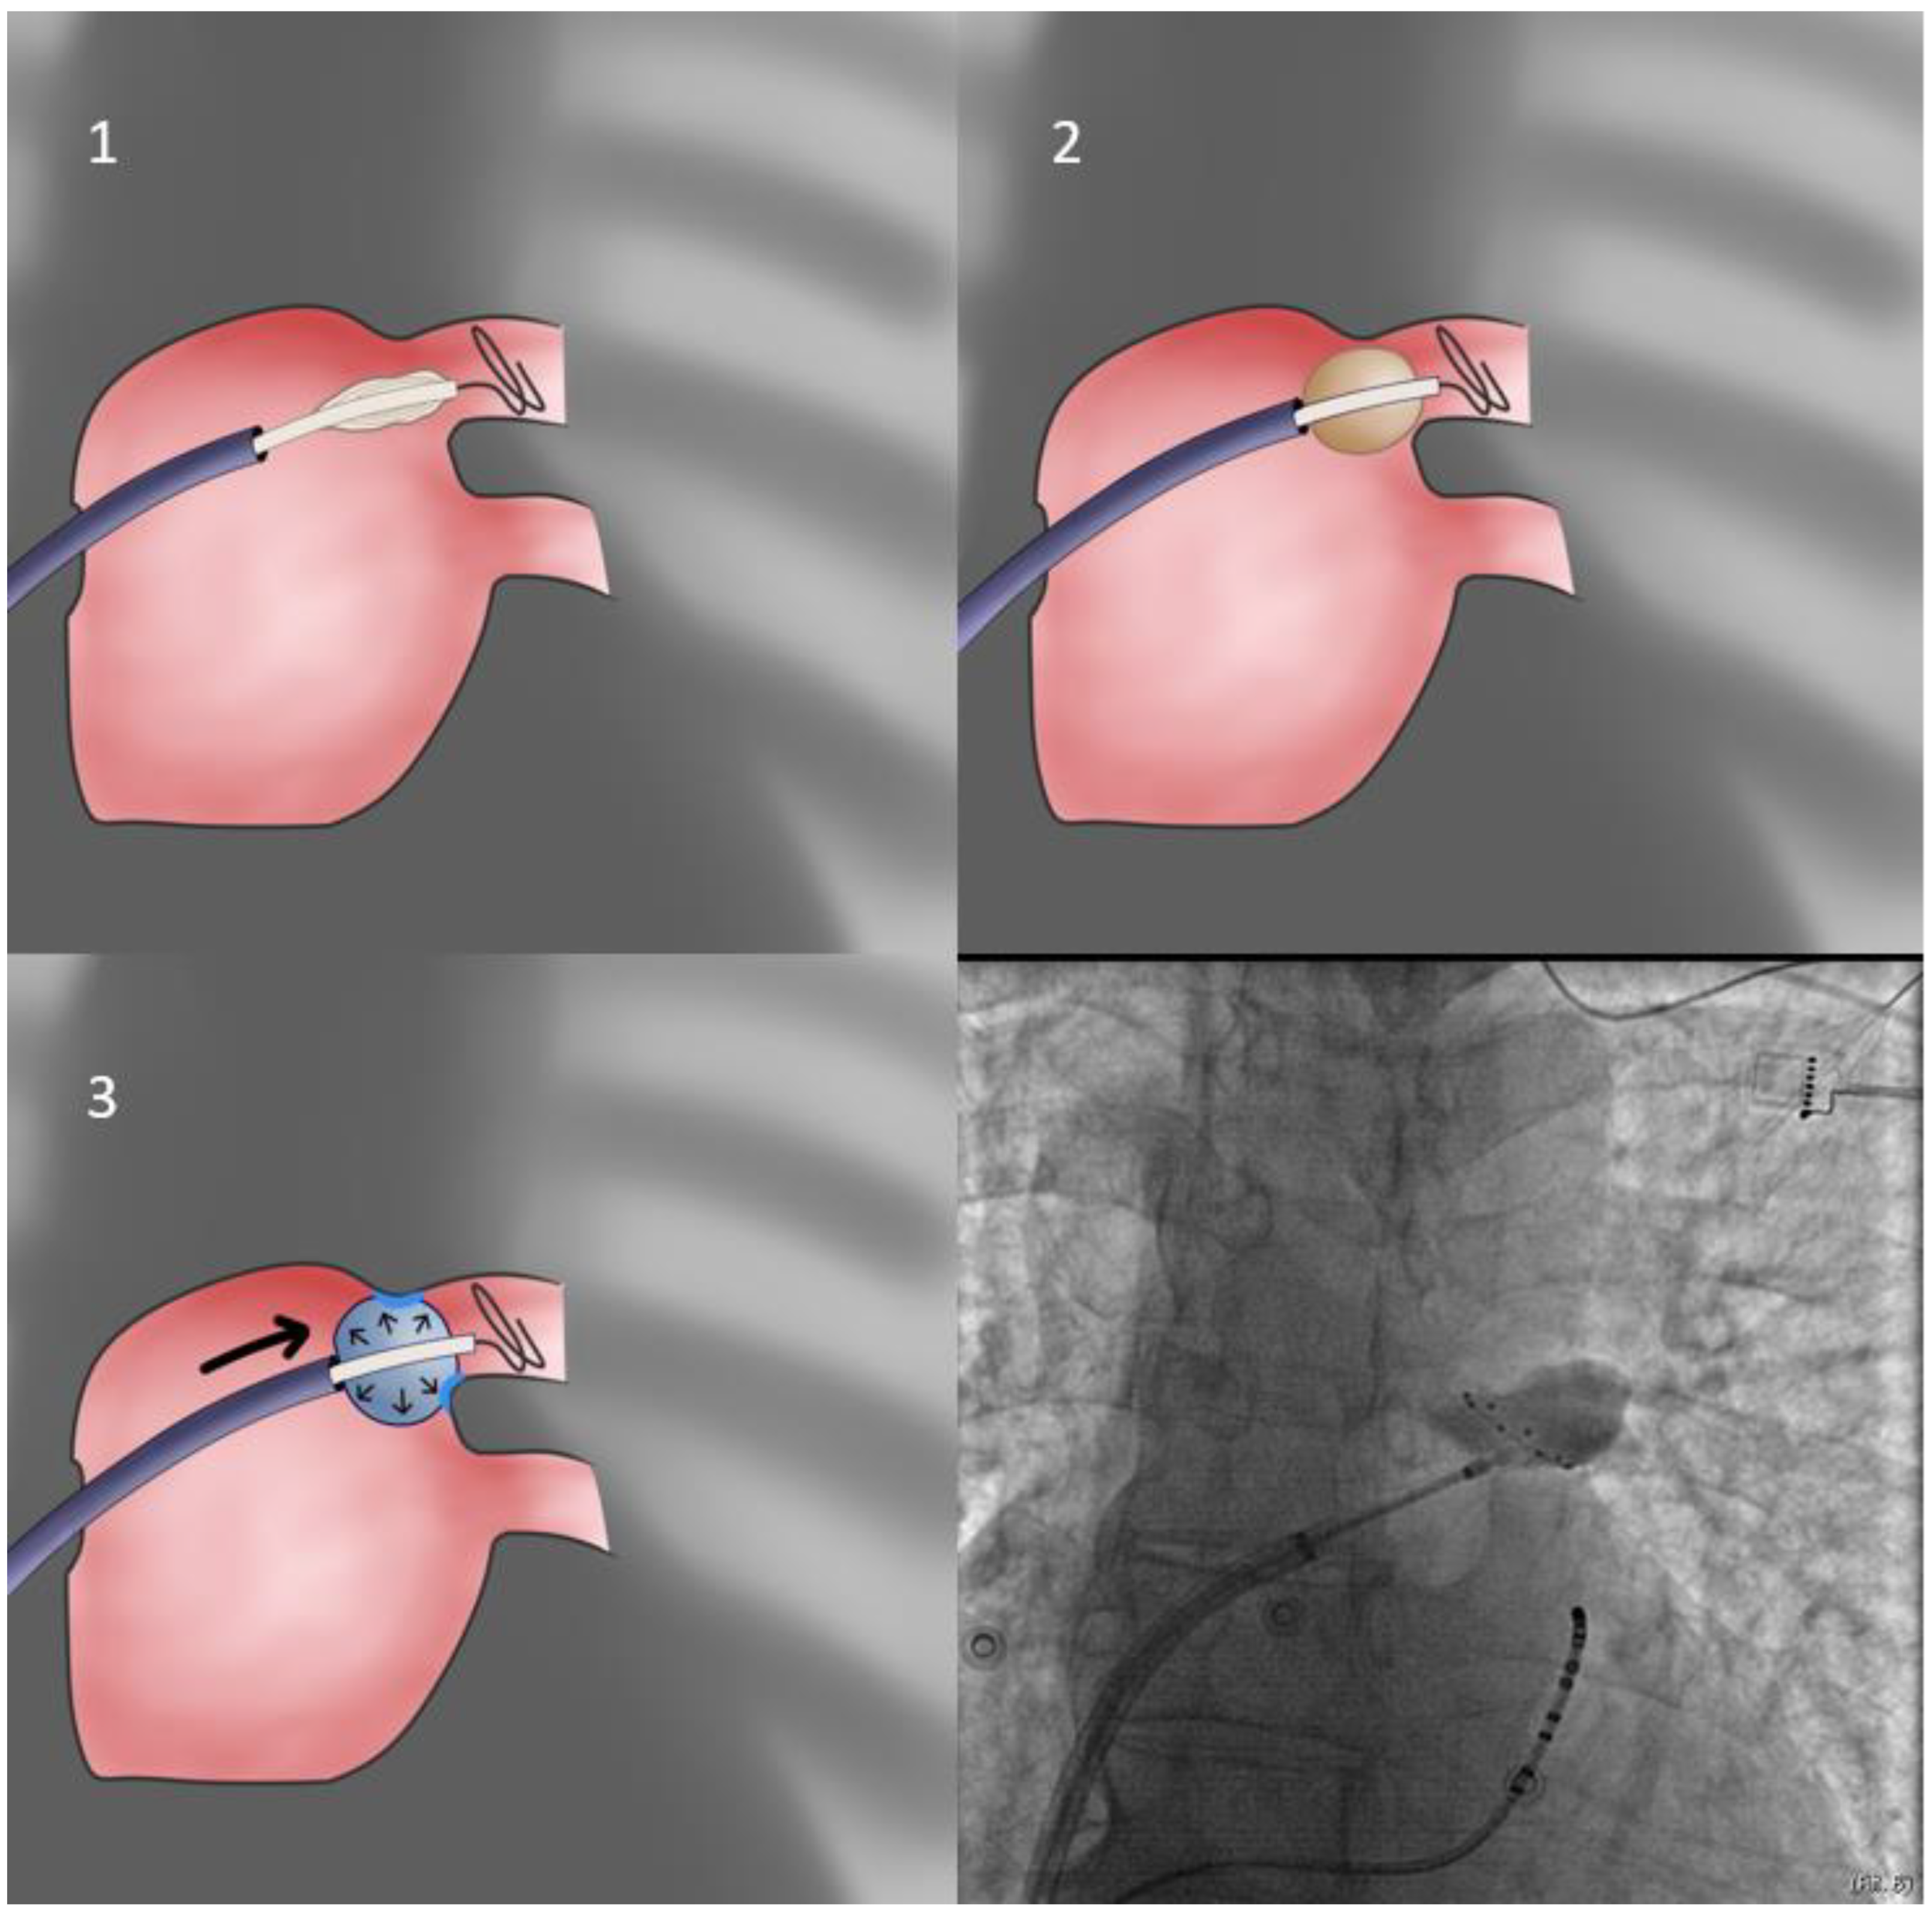

- When, despite all efforts and maneuvers already described, the operator cannot achieve proper alignment of the Achieve/CB/sheath system with the vein, a final solution entails allowing the PV itself to position the CB in its antrum. This is achieved by purposefully and warily inflating slightly inside the PV ostium (obviously the operator must be alert and retract the system if severe CB distortion is observed), whilst the sheath is placed in the approximately anticipated orientation, slightly flexed in order to be rigid. It is expected that the PV will eject the inflating balloon while imparting its orientation to it—thus, the operator must be vigilant and immediately use the prepped sheath to intercept the motion and achieve apposition of the CB to the antrum in the vein-determined orientation (trap-based approach—Figure 5). If more pressure is needed to achieve occlusion, it is more prudent to use the balloon catheter shaft since pushing the rigid sheath may undo the achieved proper orientation of the system.